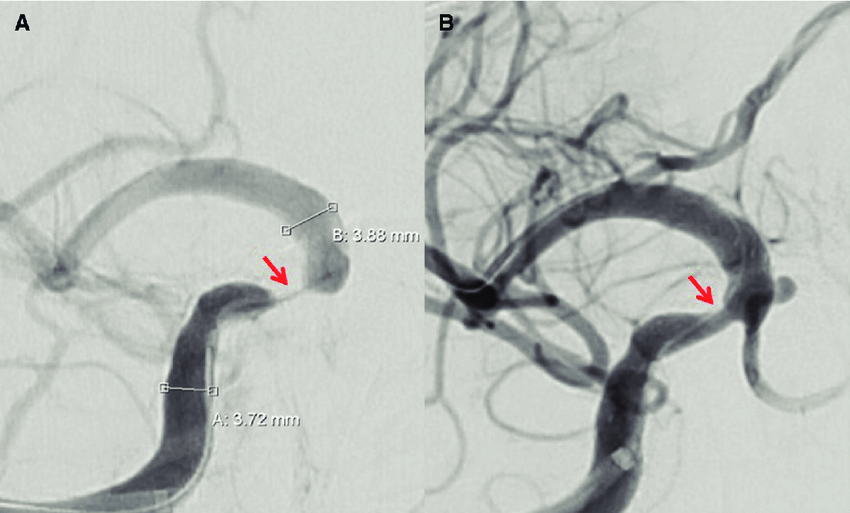

Tratamiento médico vs stent en la estenosis arterial intracraneal grave y sintomática

En los pacientes con accidente isquémico transitorio o accidente cerebrovascular isquémico debido a estenosis aterosclerótica intracraneal grave sintomática, la adición de angioplastia transluminal percutánea y colocación de stent al tratamiento médico, en comparación con el tratamiento médico solo, no produjo diferencias significativas en el riesgo de accidente cerebrovascular o muerte. JAMA, 9 de agosto de 2022.